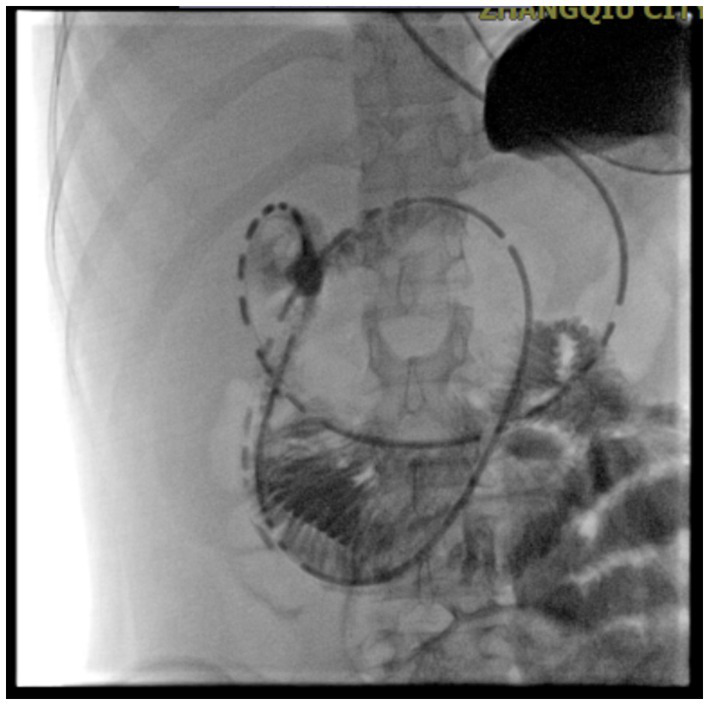

Gastrointestinal obstruction: On July 14, 2025, the patient developed the first episode of bowel obstruction, with severe abdominal distension and reduced bowel sounds at 1 per minute. An abdominal X-ray in the upright position showed gas accumulation and bowel dilation, observed during gastrointestinal tube placement (Figure 4). CT scan revealed air-fluid levels in part of the small bowel. Abdominopelvic CT showed diffuse small bowel dilatation with air–fluid levels without an identifiable transition point or mechanical obstructing lesion, and there was no imaging evidence of volvulus, hernia, or mass. After gastrointestinal decompression, enteral nutrition was administered, and the patient’s condition improved. She gradually resumed a liquid diet and then a normal diet, while continuing treatment for MELAS. Despite this, the patient experienced a second episode of bowel obstruction from August 20 to August 23, 2025, with progressive abdominal distension, absence of gas or stool passage, abdominal pain, nausea, and vomiting. Repeat CT again demonstrated marked bowel dilatation with air–fluid levels without a definite transition point or obstructing lesion, supporting the diagnosis of acute intestinal pseudo-obstruction rather than mechanical obstruction. (Figure 5). The patient was unable to take oral anticonvulsant medications, so diazepam was administered intravenously via a micro-pump. A nasogastric tube was inserted for decompression, and a small-bowel decompression tube was placed under interventional guidance (Figure 6). After 12 days of treatment with enema, enteral and parenteral nutrition, the patient’s bowel function gradually recovered. Bowel sounds returned to normal, and she was successfully discharged after transitioning to a normal diet. A follow-up phone call 16 days post-discharge revealed no adverse events.

Figure 6

Small bowel decompression. Small-bowel decompression tube inserted under interventional guidance.

In addition to stroke-like episodes, acute intestinal pseudo-obstruction (AIPO) is an uncommon manifestation of mitochondrial encephalomyopathy. Intestinal pseudo-obstruction, first described by Dudley et al. (16) in 1958, is a disabling motility disorder characterized by severe symptoms and signs of intestinal obstruction, such as abdominal pain, distention, nausea, and vomiting, along with radiographic evidence of bowel dilation in the absence of any mechanical obstruction. While typically regarded as a small-bowel motility disorder, pseudo-obstruction can occur anywhere in the gastrointestinal tract. It can present as either an acute condition, such as Ogilvie syndrome, or a chronic, remitting, or persistent disorder. In cases of small bowel obstruction, the inability to administer oral medications complicates treatment. Seessle et al. (17) reported a case of a 26-year-old MELAS patient who developed acute paralytic ileus. Conservative treatments proved ineffective, but high-caloric parenteral nutrition through a central venous catheter resulted in rapid clinical improvement. Similarly, Nakae et al. (18) described a MELAS patient with chronic intestinal pseudo-obstruction (CIPO) who showed improvement after receiving distigmine bromide, which may work by targeting acetylcholine receptors on the interstitial cells of Cajal to enhance bowel motility. Kawano et al. (19) also reported a 51-year-old MELAS patient with CIPO whose symptoms, including nausea, vomiting, and abdominal distension, gradually improved following treatment with acotiamide. The mechanisms of intestinal dysmotility in MELAS may be linked to mitochondrial dysfunction affecting smooth muscle cells and the enteric nervous system, leading to impaired motility. Reduced mitochondrial ATP production and lactate accumulation, common in MELAS, may weaken the contractility of intestinal smooth muscle, contributing to intestinal pseudo-obstruction. Mitochondrial dysfunction may also affect the enteric nervous system, disrupting the regulation of gut motility (14). Our patient experienced two episodes of intestinal obstruction. The first episode occurred during a period of critical illness, with the patient being exposed to sedatives and systemic stress, which may have contributed to the development of paralytic ileus. To exclude mechanical obstruction, an abdominopelvic CT scan was performed, with careful evaluation for a transition point. The results showed diffuse small bowel dilatation with air–fluid levels but no obstructing lesion, no definite transition point, and no imaging evidence of volvulus, hernia, or mass. A surgical consultation was obtained, and it was determined that mechanical obstruction was unlikely. The patient was therefore managed as having acute intestinal pseudo-obstruction (AIPO). Despite initial conservative treatments, including total parenteral nutrition and gastrointestinal decompression, the symptoms showed limited improvement. After the neurological condition stabilized, and with the discontinuation of sedatives and analgesics, the second episode of bowel obstruction occurred, reinforcing that the condition was unlikely to be related to ICU-associated ileus. This recurrence of non-mechanical intestinal dysmotility, in the absence of persistent electrolyte imbalances or other ICU-related factors, further supports the diagnosis of MELAS-related intestinal involvement rather than a transient ICU-associated ileus. After jejunal decompression tube insertion, the symptoms improved. Therefore, early insertion of a jejunal decompression tube can be an effective treatment option when a MELAS patient presents with acute intestinal obstruction.